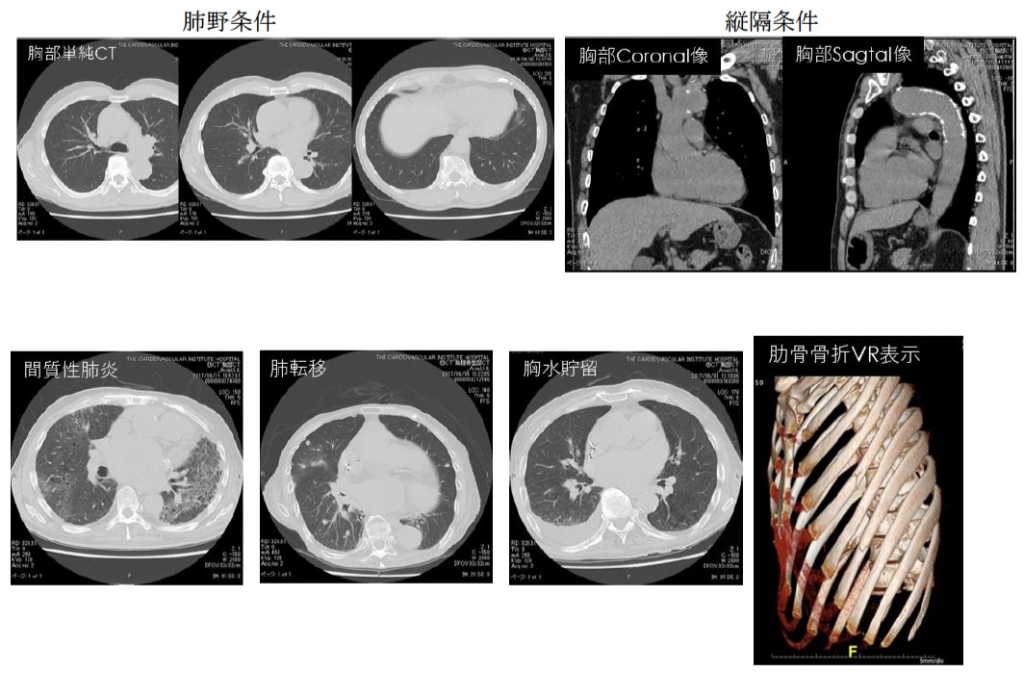

胸部CT

肺野病変や胸部動脈病変などの診断を行います。早期の肺がんなど胸部X線だけでは発見しにくい小さな病変の診断にとても有用です。

肋骨、椎体などの骨もVR画像を用いることでレントゲンでは見えにくい部位の観察が可能になります。

胸部単純CTの検査時間は5分程度で、旧64列CTと比べ1/2程度の非常に少ない被ばく量での検査が可能です。